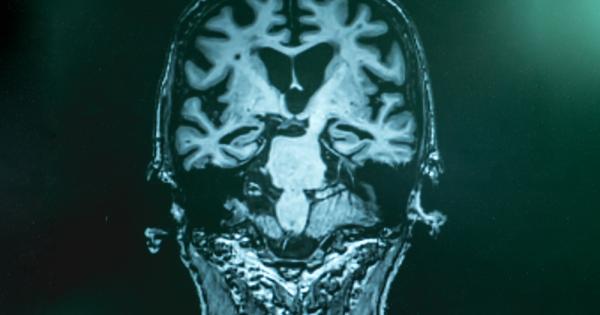

Токсични останки от опити на мозъка да се бори с

...... такова нещо се случва в човешкия мозък. Предвидени са планове и финансиране, включително проект с множество научни центрове за изследване на човешки мозъци. Източник: Мениджър Нюз